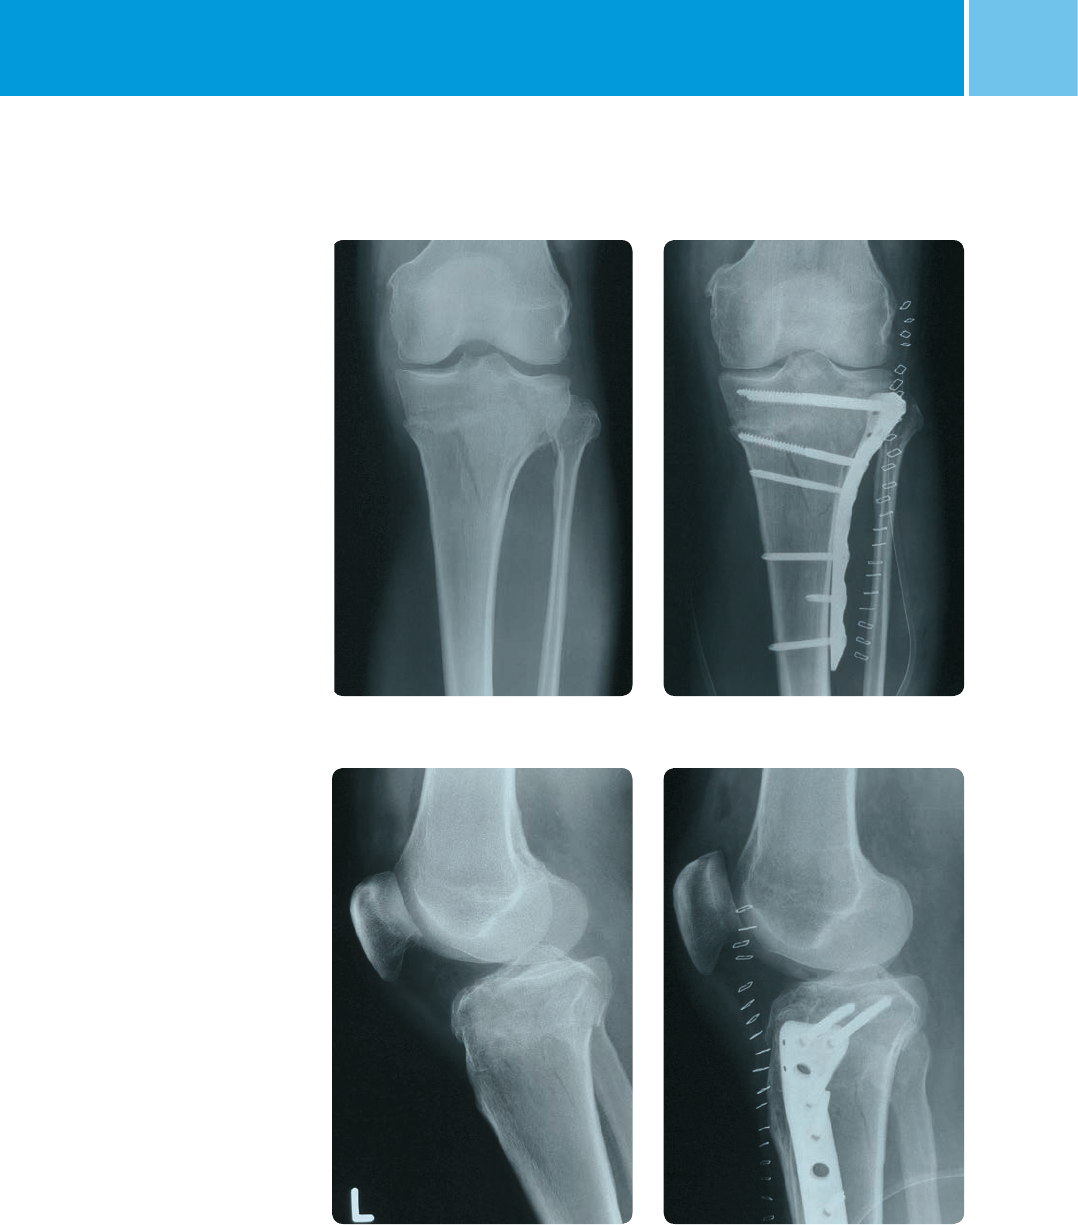

Sample Cases

Case 1: 41-C1 fracture

(OTA classification)

Postoperative

Preoperative